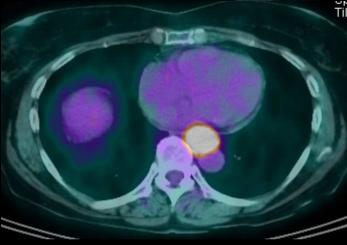

- Bilan d'extention du meme cas en Pet

/CT : Image tres net du tumeure de oesophage 1/3

moyen avec metastase ganglionaire, du foie ,

reins , ganglion pelviene et des os

|

PET /scan en

coupe axilaire |

PET/CT scan : Adeno carcinome

de oesophage . Extention ganglionaire et extention

metastasique . |